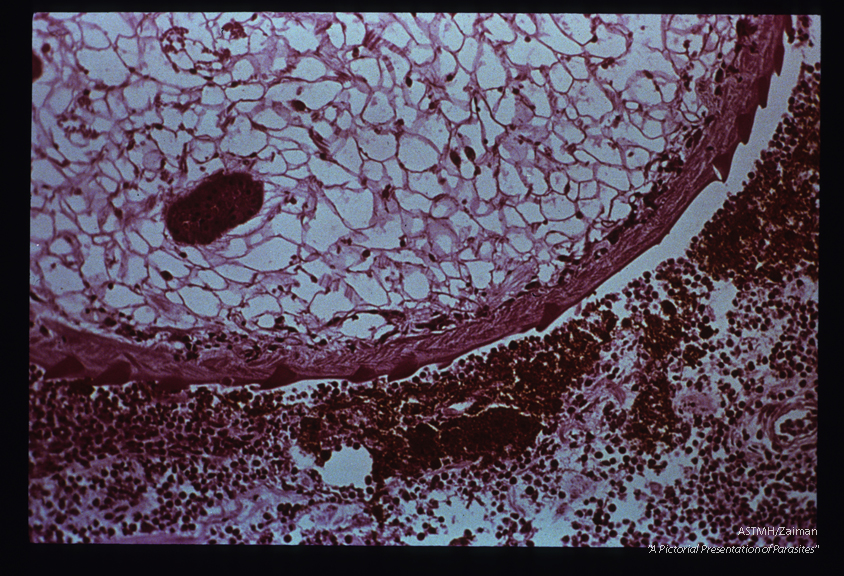

Adult embedded in intestinal wall. The parasite presents as an oval to round mass limited by a spined cuticle. The parasitic parenchyme is punctuated by multiple sections through gut (reddish-brown). The two centrally located tubular structures, separated by a light staining muscular sucker, are part of the reproductive apparatus of the parasite. A marked inflammatory response is present in the adjacent host tissues and fresh red blood cells can be seen near the parasite.

Fasciola hepatica